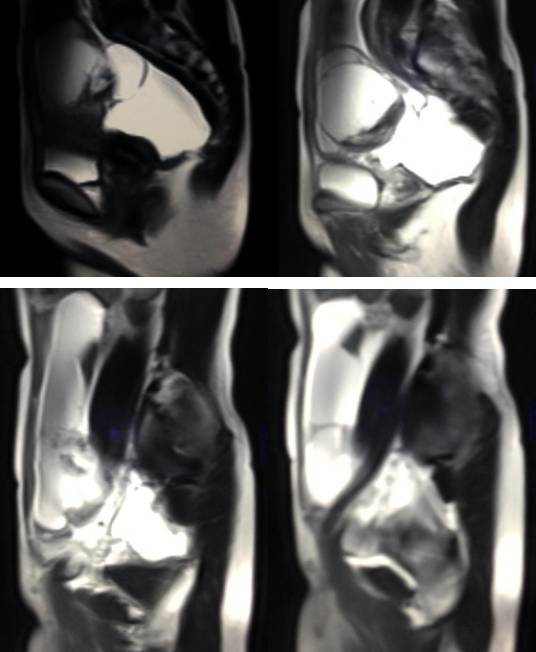

MR检查:

病理结果:黄体血肿

根据时间不同MR信号也有所不同,TIWI脂肪抑制序列可以鉴别脂肪和出血。

卵巢囊肿:呈均匀的T1WI 低信号,T2WI 高信号,边界清楚,壁薄,大多数病灶直径≤5 cm,但囊肿的起源及定性诊断困难。

功能性囊肿:因囊肿内容物成分不同,信号可有改变,随访观察数月后其信号和大小可出现变化或消失。

巧克力囊肿:常呈多发的单囊或多囊改变,病灶大小不等,囊壁厚薄不均,囊内信号复杂,囊内或各囊腔间血液因出血时期不同,信号常呈多样性,囊肿内反复出血、破裂,形成相互粘连的多房性囊肿,是其较为特征性的表现。

在鉴别卵巢畸胎瘤、出血性囊肿或巧克力囊肿时,MR 脂肪抑制T1WI 可明确肿块内高信号成分是脂肪还是出血,同时由于脂肪策划与非脂肪策划的共振频率不同,在两者交界处沿磁场频率编码方向出现化学位移伪影,但出血性囊肿与巧克力囊肿的鉴别有时较为困难。